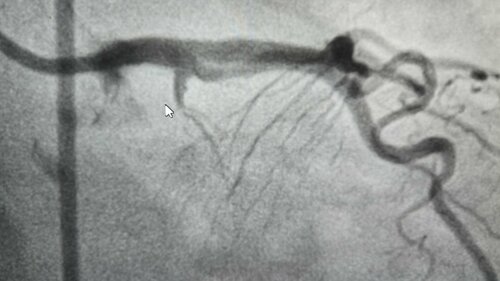

Complex LAD Angioplasty Performed by Dr. Hasmukh Gujar

Dr. Hasmukh Gujar successfully performed a complex angioplasty at Bharti Hospital, addressing a challenging case of LAD-CTO in the proximal segment. D...